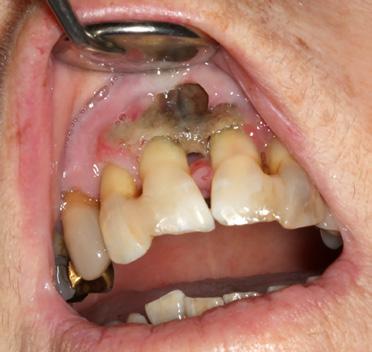

avancés, la sclérose s'étend à des parties plus importantes de l'os maxillaire. Si l'os s'infecte, cela peut entraîner une ostéolyse, la formation de séquestres et de fistules, voire une fracture pathologique. Dans le cas de la DIONJ avancée (à partir du stade 1), l'os maxillaire est exposé en un ou plusieurs endroits de la cavité buccale (illustrations 2 et 3). Les patient-e-s

peuvent alors être largement asymptomatique ou ressentir des douleurs faibles à fortes. L'ampleur des douleurs dépend principalement de l'étendue de la nécrose et d'une éventuelle inflammation concomitante (stade 2) ou d'autres complications (stade 3) (illustrations 4 et 5).

Ostéonécrose induite par les bisphosphonates apparue spontanément au niveau de la mandibule gauche chez une patiente après plusieurs années de traitement par ibandronate (Bondronat®) pour un cancer du sein métastatique (stade 1)

Bei der fortgeschrittenen DIONJ (ab Stadium 1) liegt der Kieferknochen an einer oder mehreren Stellen der Mundhöhle frei (Abbildungen 2 und 3). Der*die Patient*in

kann dabei weitgehend beschwerdefrei sein oder wenig bis starke Schmerzen verspüren. Das Ausmass der Beschwerden hängt dabei hauptsächlich von der Ausdehnung der Nekrose und von einer allfälligen Begleitentzündung (Stadium 2) oder weiteren Komplikationen (Stadium 3) ab (Abbildungen 4 und 5).

Abbildung 2: Spontan aufgetretene Bisphosphonatinduzierte Osteonekrose am linken Unterkiefer bei einer Patientin nach mehrjähriger Therapie mit Ibandronat (Bondronat®) wegen einer metastasierenden Brustkrebserkrankung (Stadium 1)